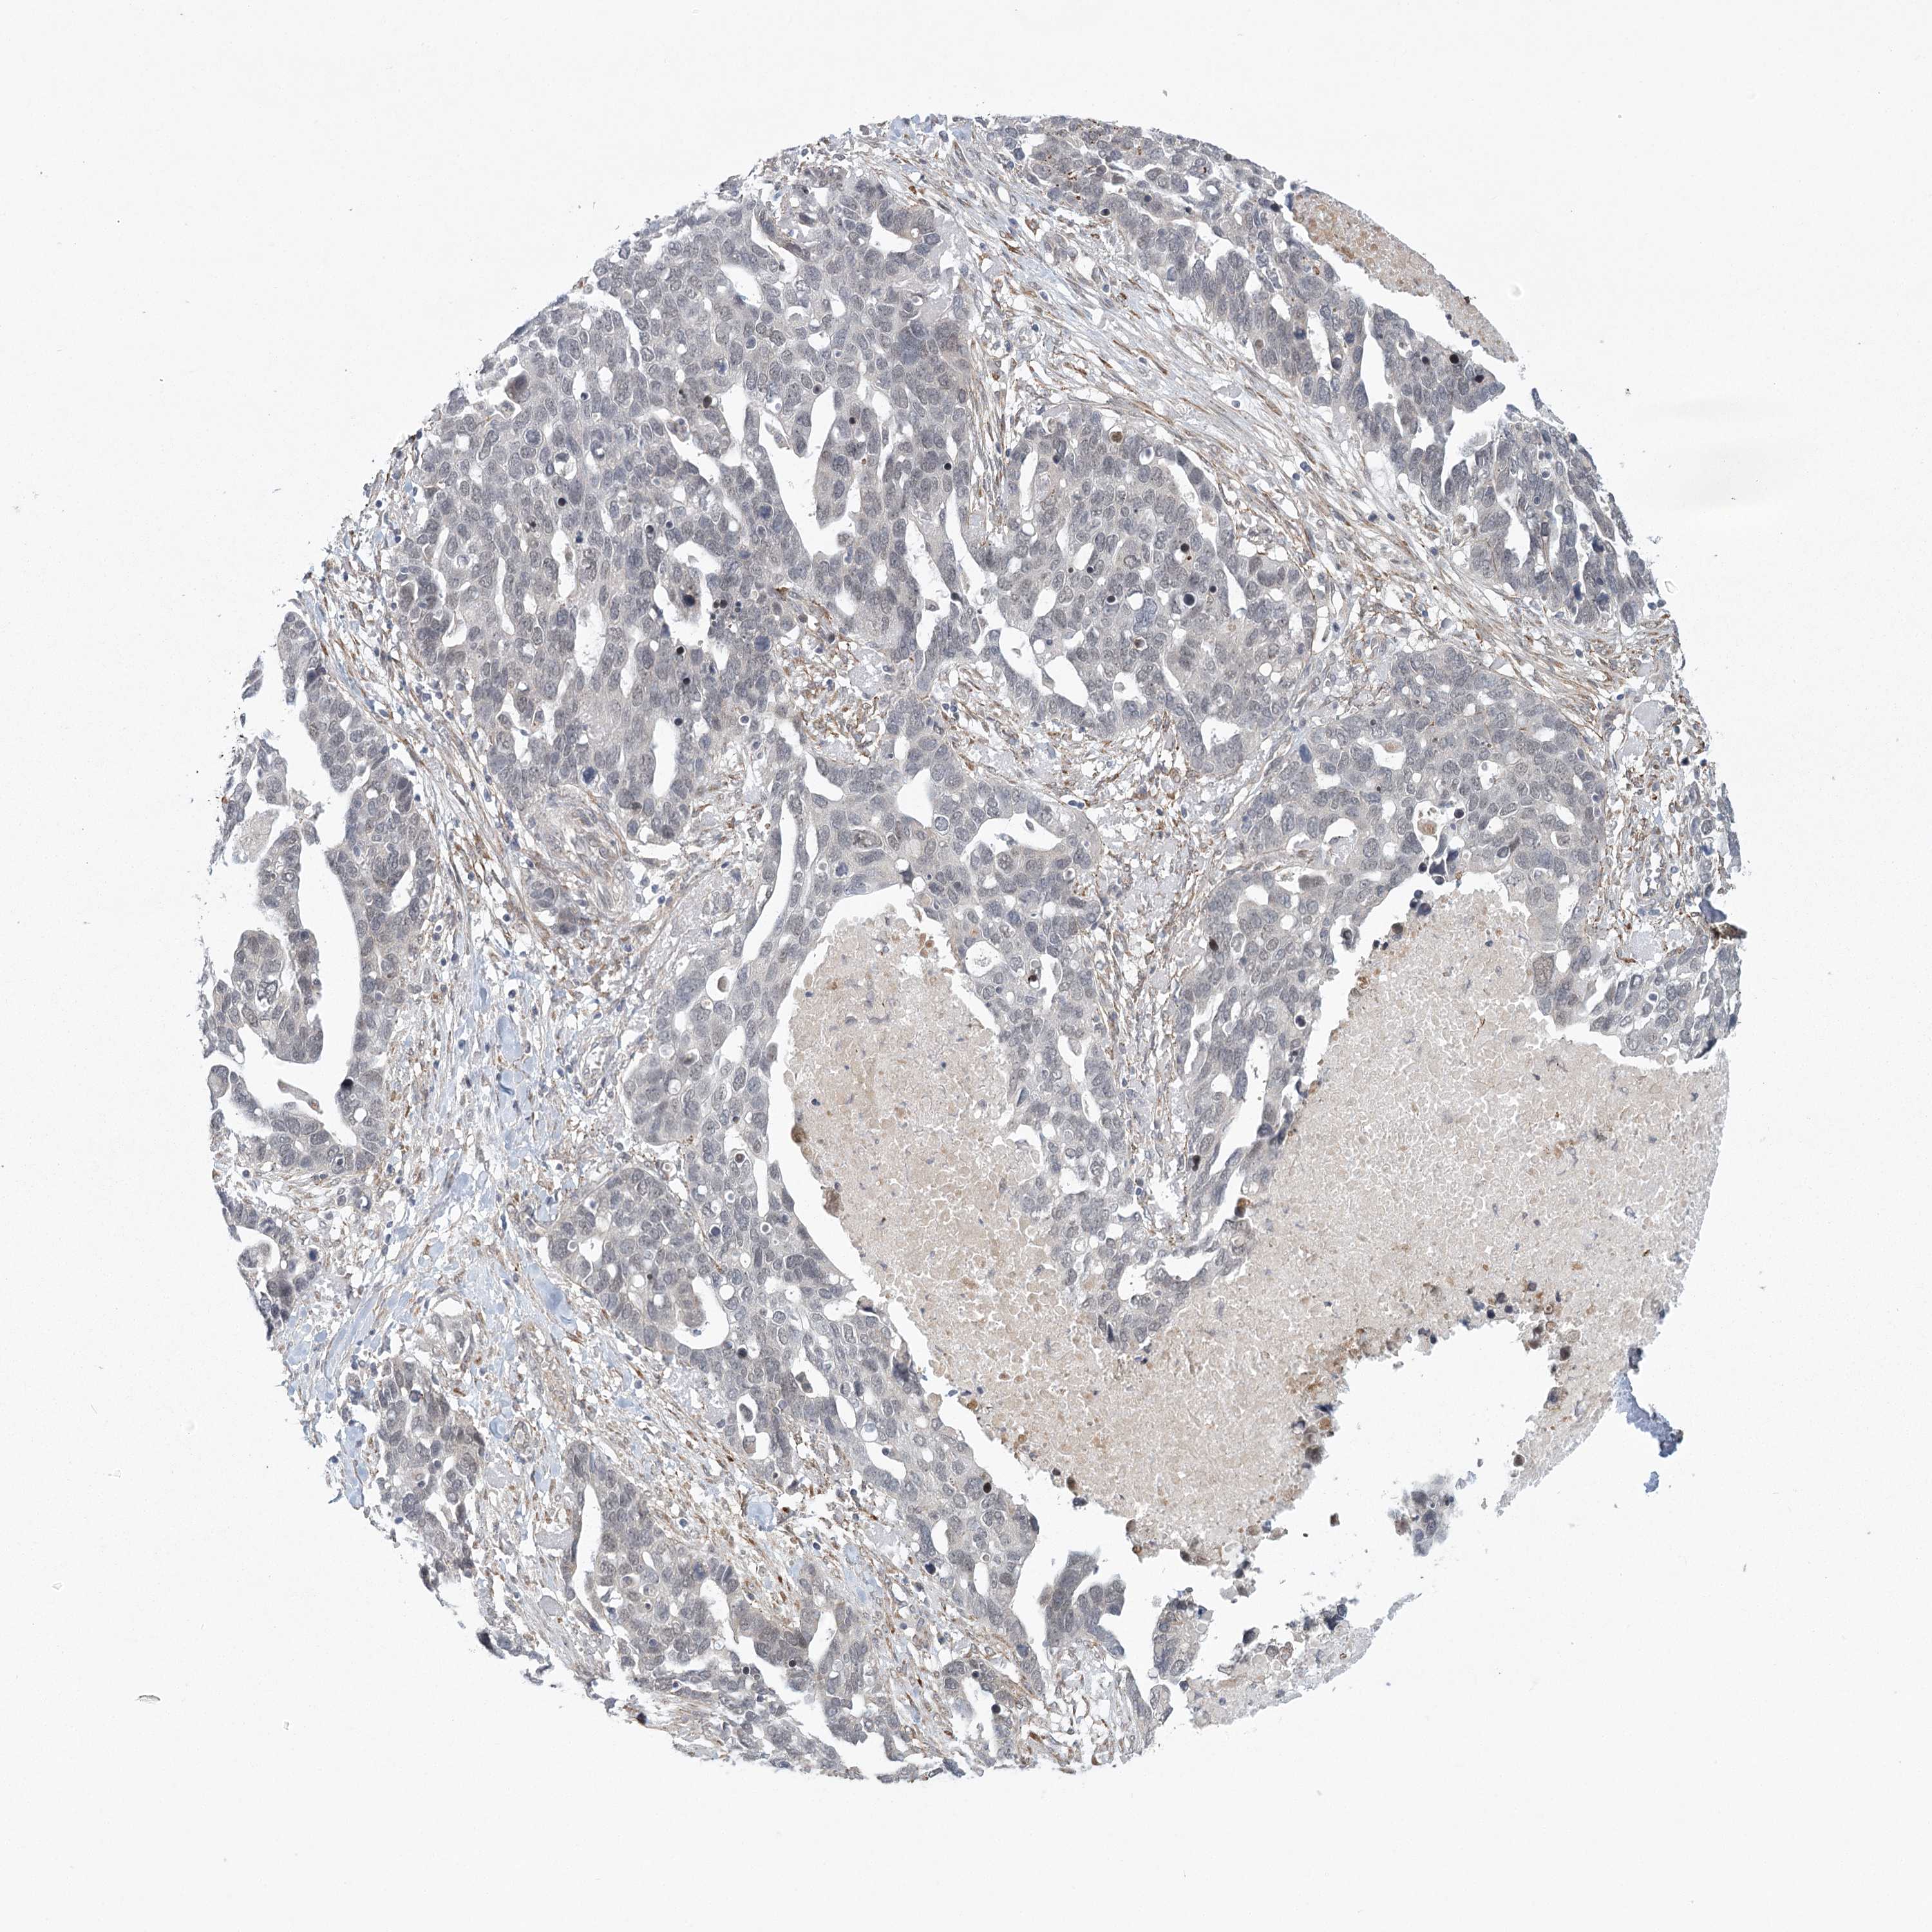

OVARIAN CANCER - Protein expressioni

A mouse-over function shows sample information and annotation data. Click on an image to view it in a full screen mode. Samples can be filtered based on level of antibody staining by selecting one or several of the following categories: high, medium, low and not detected. The assay and annotation is described here.

Note that samples used for immunohistochemistry by the Human Protein Atlas do not correspond to samples in the TCGA dataset.

Antibody stainingi

Antibody staining in the annotated cell types in the current human tissue is reported as not detected, low, medium, or high, based on conventional immunohistochemistry profiling in selected tissues. This score is based on the combination of the staining intensity and fraction of stained cells.

Each image is clickable and will lead to virtual microscopy that enables deeper exploration of all samples and also displays staining intensity scores, fraction scores and subcellular localization as well as patient and tissue information for each sample.

Antibody HPA035900

Antibody HPA035901

Cystadenocarcinoma, mucinous, NOS